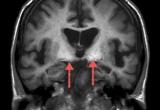

Российские ученые смогли открыть причину эпилептических приступов, их работе посвящена статья в журнале Frontiers in Cellular Neuroscience. Специалисты связали их с патологией в работе рецепторов, передающих сигналы в мозге...